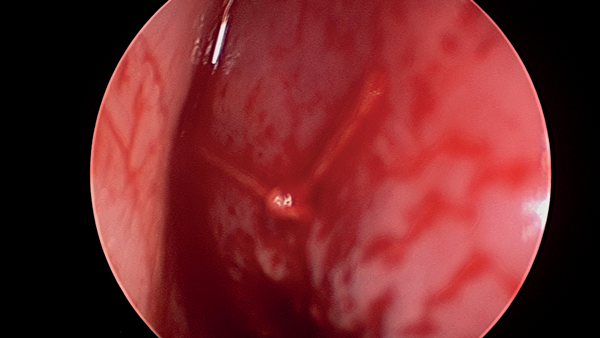

The septal flap elevation is continued dorsally between the superior edge of the perforation and the upper lateral cartilage. The upper lateral cartilage is then separated from the septum extramucosally using a no. 15 blade. At this stage, one can appreciate the definite advantage of the open approach, as lateral retraction of the upper lateral cartilages provides better visualisation of the dorsal and posterior septum, allowing the flap elevation above and behind the perforation to be conducted under direct vision (Figure 2).

Figure 2: Exposure of dorsal and posterior septum.